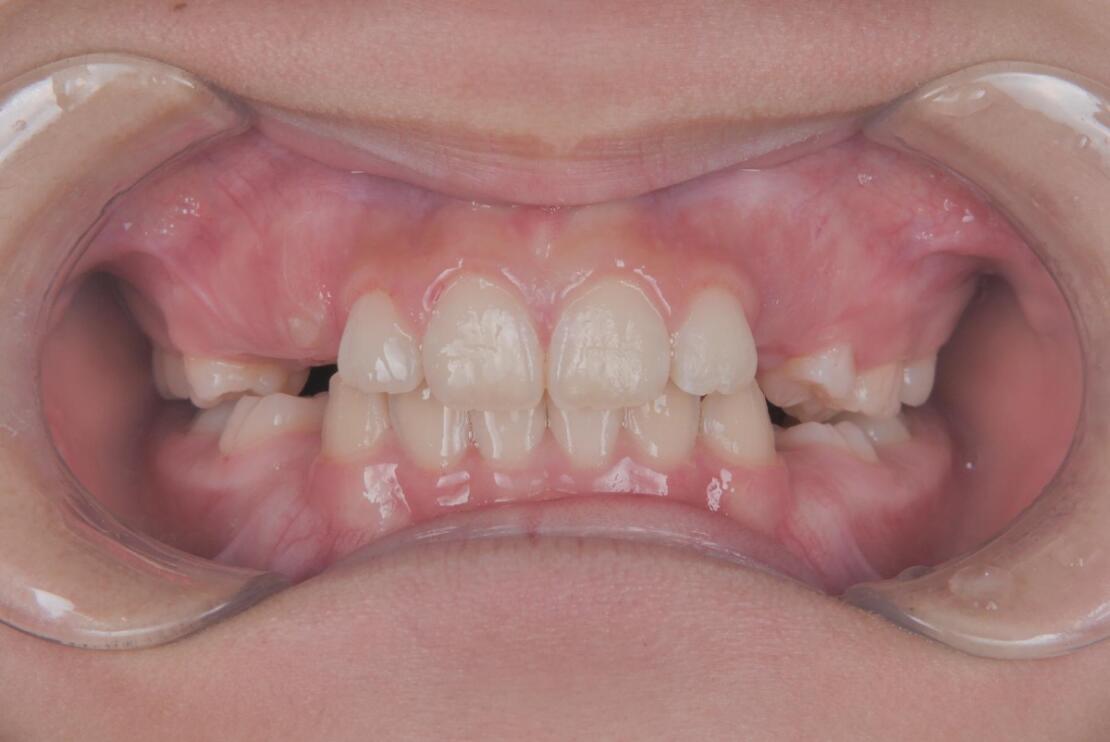

スタート時8歳の女の子の症例です。主訴は歯並びのガタつきと、上の2番目の歯が八重歯のようにハの字に傾いていることでした。

BEFORE